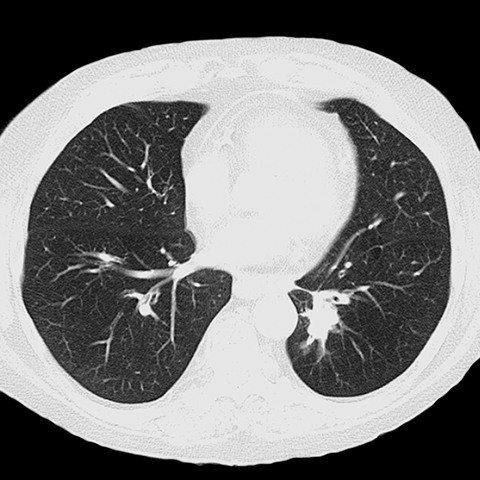

Subtle LLL Retrocardiac Opacity (Chest CT, Lung Window) [2 of 2]